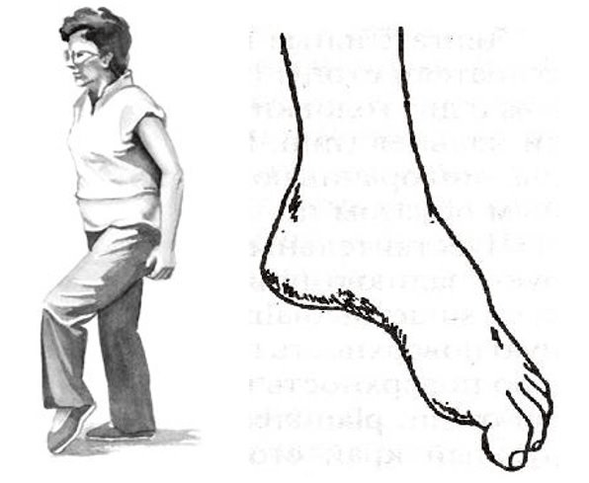

Most often, such abnormalities appear in the legs, with protrusions and hernias of the lumbar spine.There are motor structures that innervate the muscles of the leg and foot.Therefore, in the case of advanced, complicated lumbar osteochondrosis, the foot can cause beating.He turns inward, the person is forced to raise his foot high so that he can step with the beating foot, this is called steppage, "rooster walk".

But the whole danger of movement disorders is that they can be isolated and do not involve pain.And if a person has "no pain", he may not get to the doctor in time.Therefore, it is very important for patients with progressive protrusions and hernias, for example in the lumbar region, to regularly walk on their toes and heels and monitor the work of their muscles.